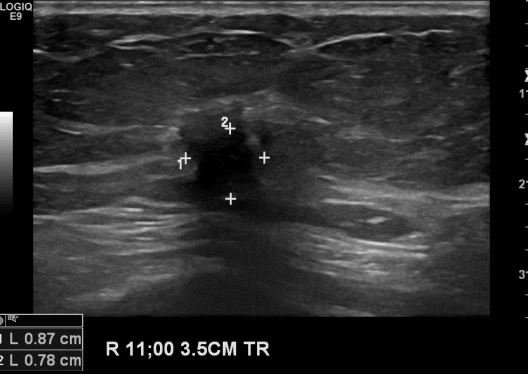

상기환자 건강검진상 이상소견을 내원하신 60대 여성분으로 우측 11시 방향 3.5cm

거리의 의심스러운 멍울 조직검사 시행하여 우측 침윤성 유관암 진단 되었습니다.